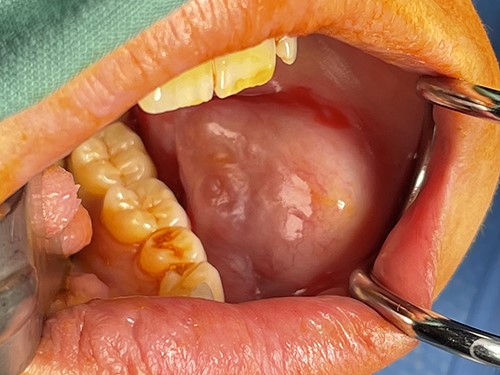

On examination, a 3 × 3cm firm mass was adjacent to the mandibular body with no cutaneous or mucosal changes. It was anterior to the parotid gland and masseter (Fig. 1). Dental examination and orthopantomogram excluded odontogenic origin. There was no palpable cervicofacial lymphadenopathy. Systemic examination was unremarkable.

The surgeon performed an intraoral excision of the lesion under general anaesthetic (Fig. 2). It was well circumscribed and confined within the buccal soft tissues. The lesion was removed intact and primary mucosal closure achieved.

Appearance of lesion following buccal sulcus incision and dissection.